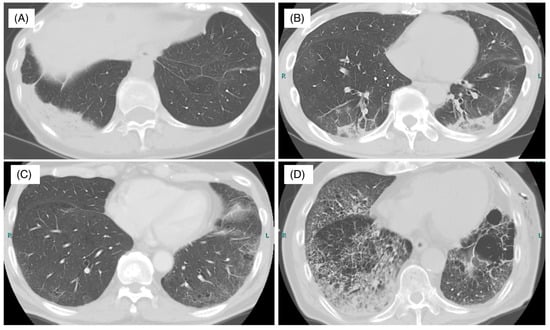

5.1. Radiographic Findings

- Nishino, M.; Ramaiya, N.H.; Awad, M.M.; Sholl, L.M.; Maattala, J.A.; Taibi, M.; Hatabu, H.; Ott, P.A.; Armand, P.F.; Hodi, F.S. PD-1 inhibitor-related pneumonitis in advanced cancer patients: Radiographic patterns and clinical course. Clin. Cancer Res. 2016, 22, 6051–6060. [Google Scholar] [CrossRef] [PubMed]